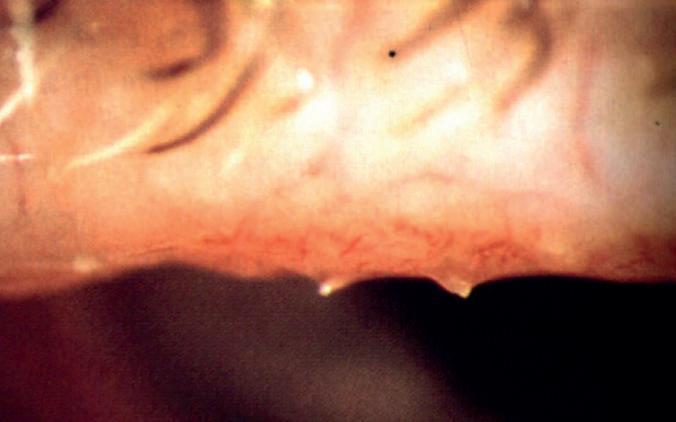

Dal video presentato all’APACRS dal Dottor Sri Ganesh, il momento del distacco zonulare